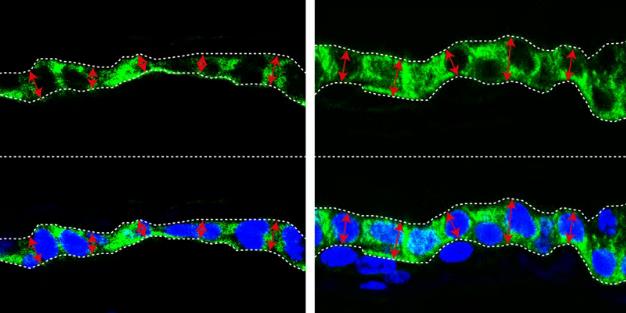

新成像技术能同步观测细胞精细结构

受真菌感染果蝇的多色电子显微镜图像。图中可见真菌的细胞核(绿色)、线粒体(紫色)以及果蝇表面的精细结构。图片来源:物理学家组织网 美国哈佛大学科学家研制出一种新型成像技术。这是一种多色显微镜技2026-03-05 -